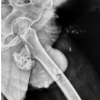

After explaining the procedure, the patient was taken for surgery for excisional biopsy. Hairs were removed from surgical site (Fig. 2a). After GA, the patient was given lateral decubitus position. A curvilinear incision was taken over swelling. Temporal fascia and temporalis muscle were incised in a “T” shape using a bipolar cautery. Bony mass reached; peduncle identified. Extraperiosteal excision of tumor with some amount of normal surrounding bone and periosteum was done using sharp 10 mm osteotome. Tumor was hard to cut. Bed of the tumor was bleeding and cauterized thoroughly. Bone wax was applied. Wound was closed in layers, no drain required (Fig. 2c). Excised part was smooth rounded (Fig. 2b) with a peduncle at one end and was bony hard on palpation with appearance suggestive of osteochondroma. Postoperatively, on check dress on day 2, there was no discharge or bleeding. The patient was given IV antibiotics. The patient was discharged on oral antibiotics and analgesics on day 3. However, histopathology showed irregularly shaped bony trabeculae in fibrous stroma of variable cellularity without accompanying osteoblast rimming (Fig. 3a, b, c). Thus, diagnosis is fibrous dysplasia of bone.